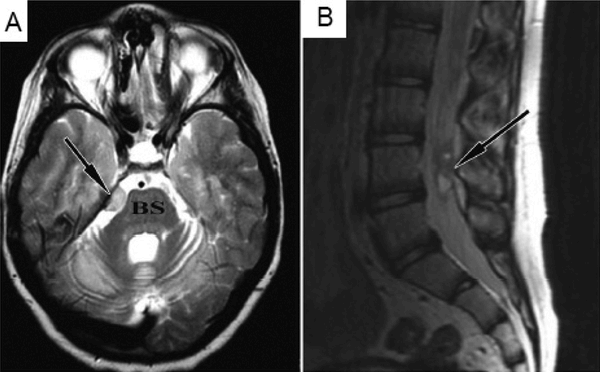

In this case report, a 9 year-old boy affected by an inherited neurodegenerative condition called ataxia telangiectasia, had been treated in Moscow with repeated transplantations of fetal neural stem cells. Four years later, the patient complained about headaches, and a brain scan investigation revealed a small tumour compressing the brain stem (BS and arrow in panel A of the image below). There were also signs of tumour growth further down the spinal cord (arrow in panel B of the image below).

Source: Ncbi

Molecular analysis of biopsies from the tumours was performed, and the results led the investigators to conclude that the tumour is derived from the neural stem cells. Luckily the slow growth suggests a relatively benign tumour which the investigators hope suggests a favourable prognosis.